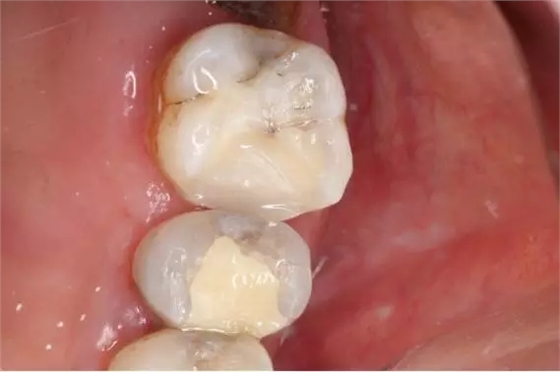

1.去除食物殘渣及大部分腐質(zhì)

640.webp (1).jpg

2.去凈腐質(zhì)后近髓狀態(tài)

640.webp (2).jpg